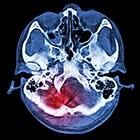

Stroke is the third leading cause of death behind heart disease and cancer in the US. Our customer, an early stage company is developing the next generation in minimally invasive neurovascular devices for the treatment of intracranial aneurysms, one of the primary causes of stroke. As a start-up seeking to quickly prove out its idea and at the same time attract funding to support development, they sought a partner that could match their own drive for speed and ingenuity. Like successful stroke treatment in the clinical setting, response time and speed were vital in our customer's development process.